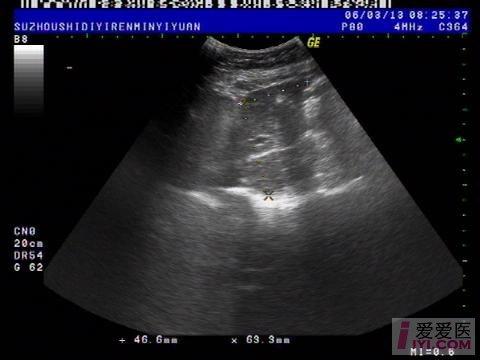

今天上午检查的一位病人, 胆囊切除术后会不会一定伴有胆总管扩张?

肝脏:左叶:长度47mm,厚度63mm 右叶:斜径106mm,形态规则,包膜完整,肝区光点细密,内部回声均匀,肝内血管走行清晰。 门静脉内径10mm。

胆囊:已切除。 胆总管:内径:11mm,胆囊窝未见积液。

1.肝未见异常。

2.胆总官扩张。